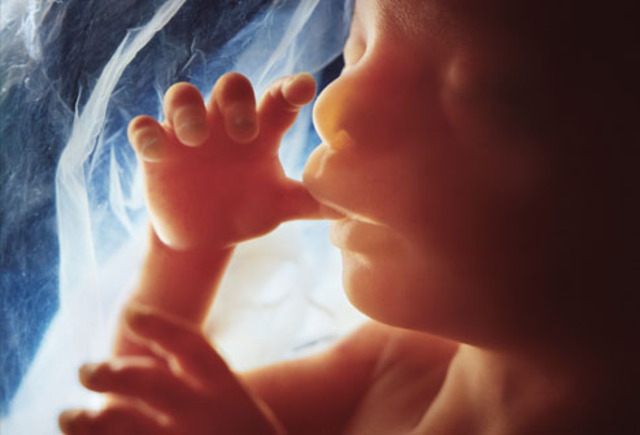

• Month 9 Baby

Month 9 Baby

About 17-18 inches (43-46 cm) long, 5-6 pounds.

Weight gain continues until the week before birth.

Skin becomes smooth as fat deposits continue.

Movements decrease as the fetus has less room to move around.

Acquires disease-fighting antibodies from the mother's blood.